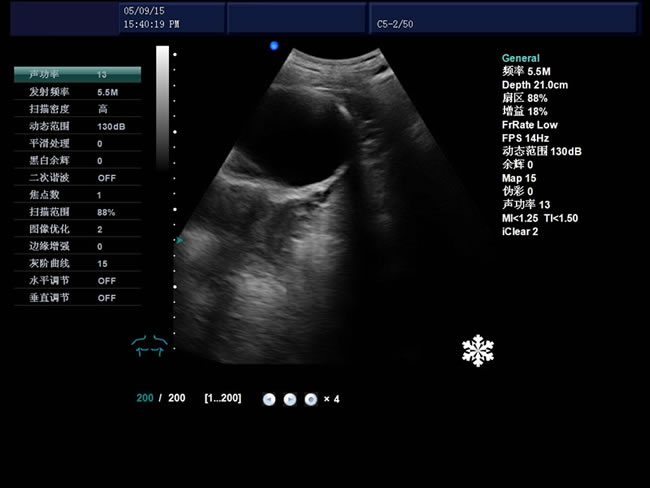

S9 彩色多普勒獸用超聲診斷儀

• S9彩色多普勒獸用超聲診斷儀是徐州市大為電子設備有限公司推出的一款全新的彩色超聲診斷儀器。

• 臨床應用